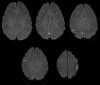

A 38-year-old patient with a prosthetic aortic valve had weeks of fever and respiratory symptoms. Although endocarditis was suspected early, numerous blood cultures and echocardiograms failed to confirm the diagnosis. Key questions were: What is a broad differential diagnosis for the above symptoms? What is unique about diagnosing prosthetic valve endocarditis compared with native valve endocarditis? What other imaging modalities are useful for diagnosing prosthetic valve endocarditis when initial echocardiographic evaluation is negative? What organisms are classically implicated in "culture negative" infective endocarditis? Serial blood cultures and multimodal imaging, including cardiac positron emission computed tomography with 18F-fluorodeoxyglucose, lead to a diagnosis of prosthetic valve endocarditis with a HACEK (Haemophilus, Aggregatibacter, Cardiobacterium, Eikenella, Kingella) pathogen. Repeat blood cultures and serial multimodal imaging are paramount to diagnosing prosthetic valve endocarditis, particularly when caused by a fastidious organism.